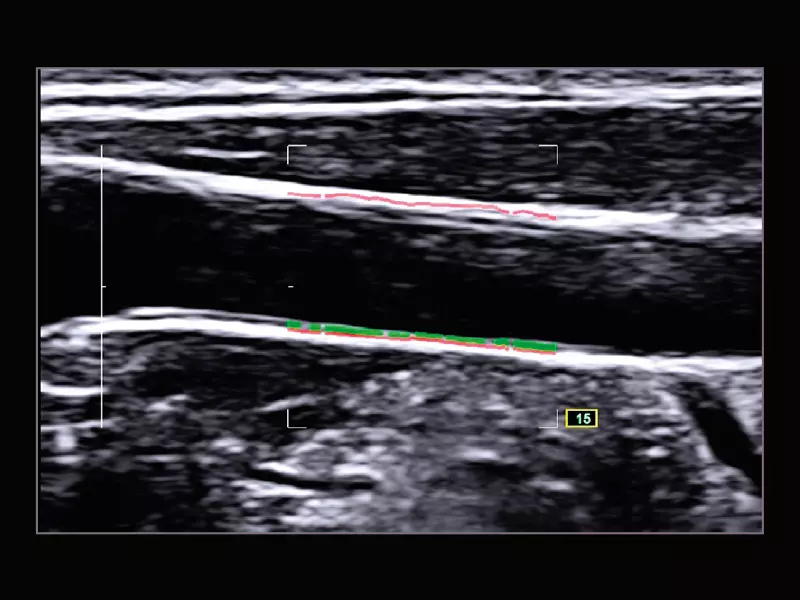

MyLab™9 Platform - QIMT Intima-media thickness quantification based on radio frequencies in real-time studies

MyLab™9 Platform - QIMT Intima-media thickness quantification based on radio frequencies in real-time studies

MyLab™X8 Platform - Real-time measurement of the Intima Media with QIMT

MyLab™X8 Platform - Real-time measurement of the Intima Media with QIMT

MyLab™X5 - QIMT

MyLab™X5 - QIMT

MyLab™X7 - QIMT

MyLab™X7 - QIMT

MyLab™Omega - RF QIMT

MyLab™Omega - RF QIMT